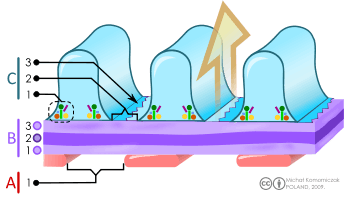

B. Glomerular basement membrane: 1. lamina rara interna 2. lamina densa 3. lamina rara externa

C. Podocytes: 1. enzymatic and structural proteins 2. filtration slit 3. diaphragma

The main function of the glomerulus is to filter plasma to produce glomerular filtrate, which passes down the length of the nephron tubule to form urine. The rate at which the glomerulus produces filtrate from plasma (the glomerular filtration rate) is much higher than in systemic capillaries because of the particular anatomical characteristics of the glomerulus. Unlike systemic capillaries, which receive blood from high-resistance arterioles and drain to low-resistance venules, glomerular capillaries are connected in both ends to high-resistance arterioles: the afferent arteriole, and the efferent arteriole. This arrangement of two arterioles in series determines the high hydrostatic pressure on glomerular capillaries, which is one of the forces that favour filtration to the Bowman's capsule.[6]

If a substance has passed through the glomerular capillary endothelial cells, glomerular basement membrane, and podocytes, then it enters the lumen of the tubule and is known as glomerular filtrate. Otherwise, it exits the glomerulus through the efferent arteriole and continues circulation as discussed below and as shown on the picture.

Permeability

The structures of the layers determine their permeability-selectivity (permselectivity). The factors that influence permselectivity are the negative charge of the basement membrane and the podocytic epithelium, and the effective pore size of the glomerular wall (8 nm). As a result, large and/or negatively charged molecules will pass through far less frequently than small and/or positively charged ones.[7] For instance, small ions such as sodium and potassium pass freely, while larger proteins, such as hemoglobin and albumin have practically no permeability at all.